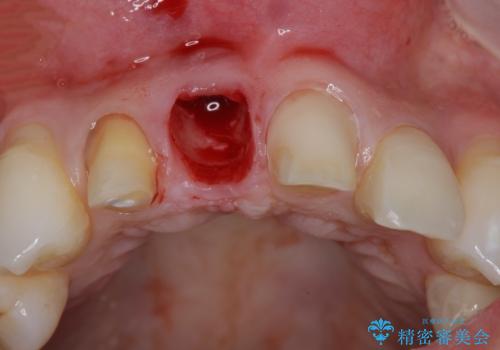

CT撮影を行った結果、右上前歯は吸収が進み抜歯が必要な状態です、

抜歯をせず放置すると、より吸収が進み臨在する歯にも悪影響を及ぼしてしまう可能性が考えられます。